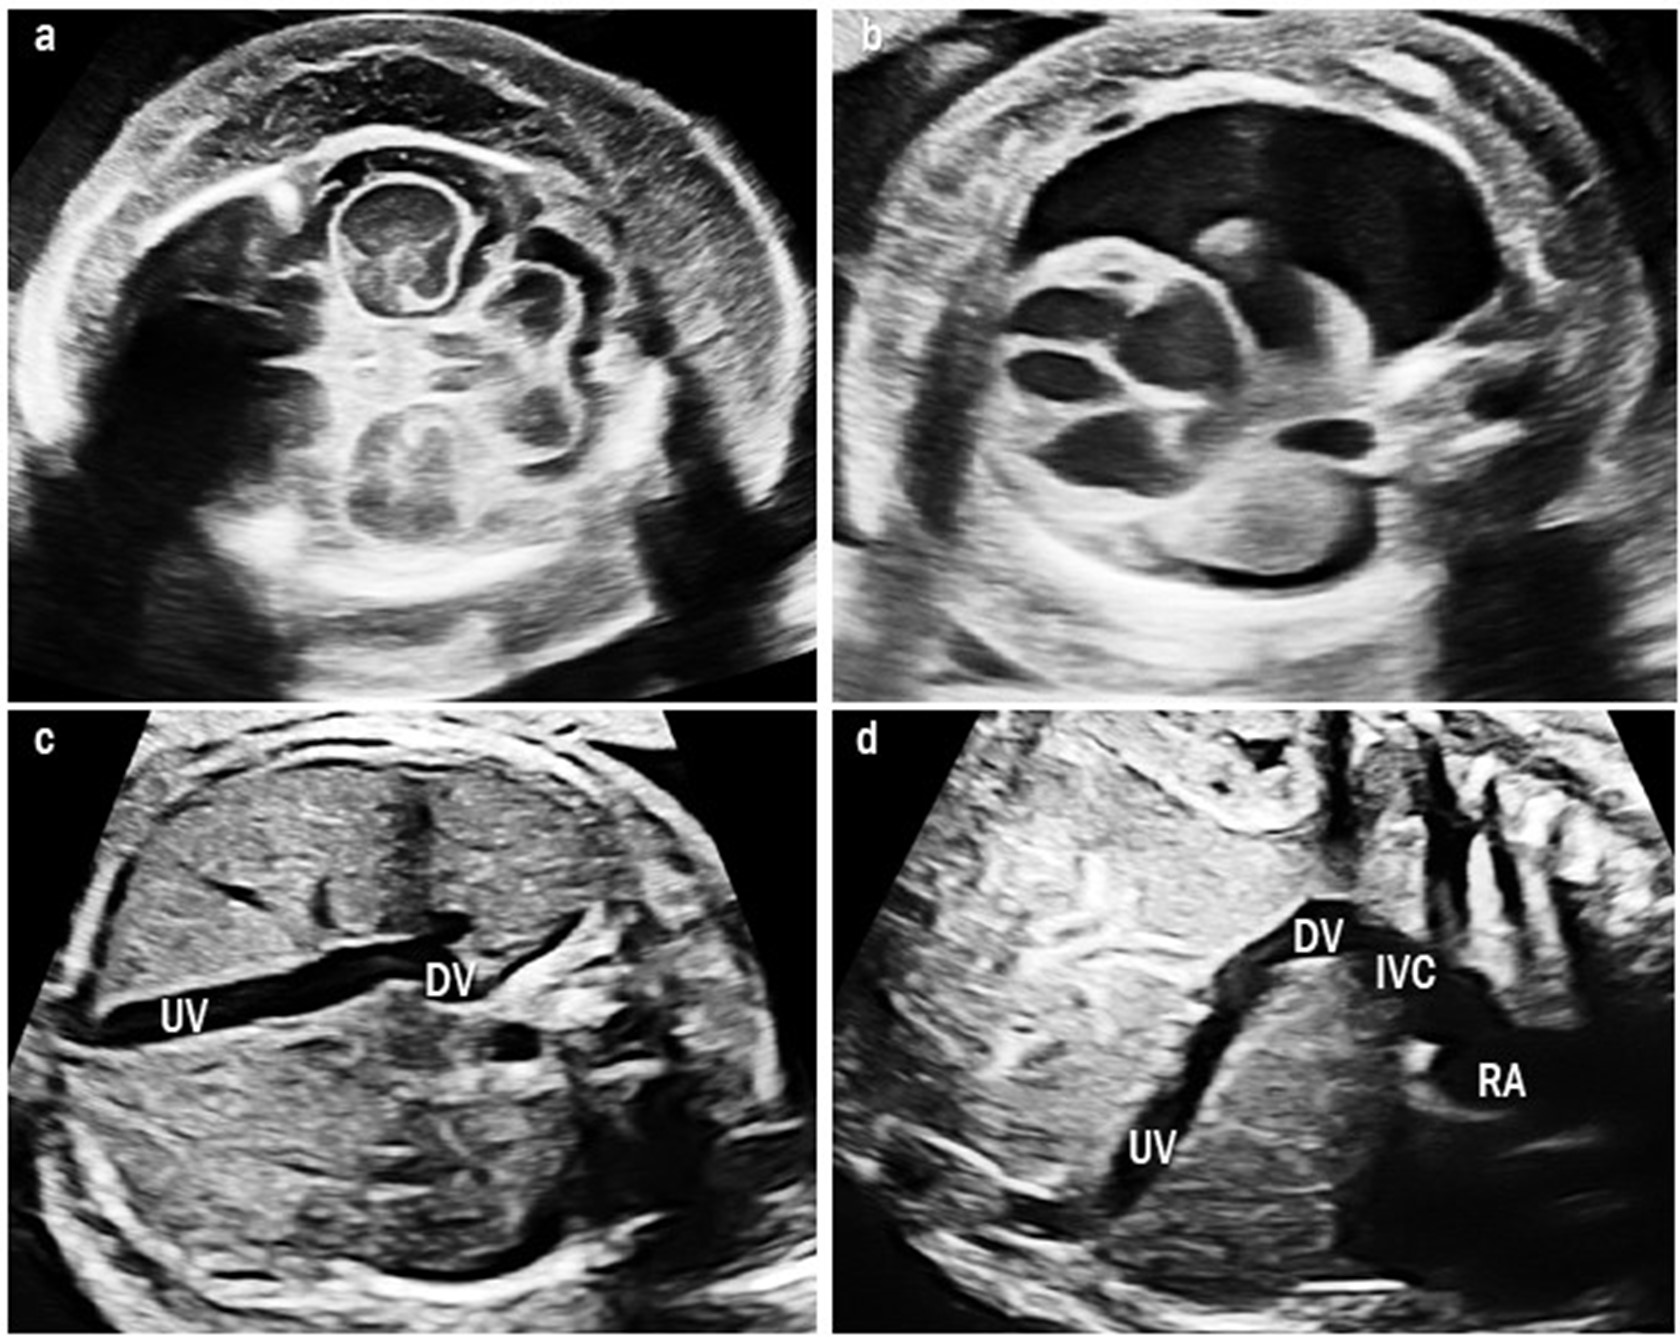

Four cases were classified as type IIIa UPSVS. They showed an abnormal connection between the PV and hepatic vein, which was observed as a tortuous and engorged vessel in the fetal liver (Fig. 4). However, the umbilical-portal-DV complex remained intact. Among these cases, three (75%) had birth weights below the 10th percentile and all had transient mild hyperammonemia. More importantly, none of them required shunt ligation surgery or liver transplantation.

Fig. 4.Intrahepatic portal-systemic shunt in case 11. (a) The tortuous and engorged hepatic vein (HV) is shown. (b) The intrahepatic portal vein (PV) is connected to the HV.